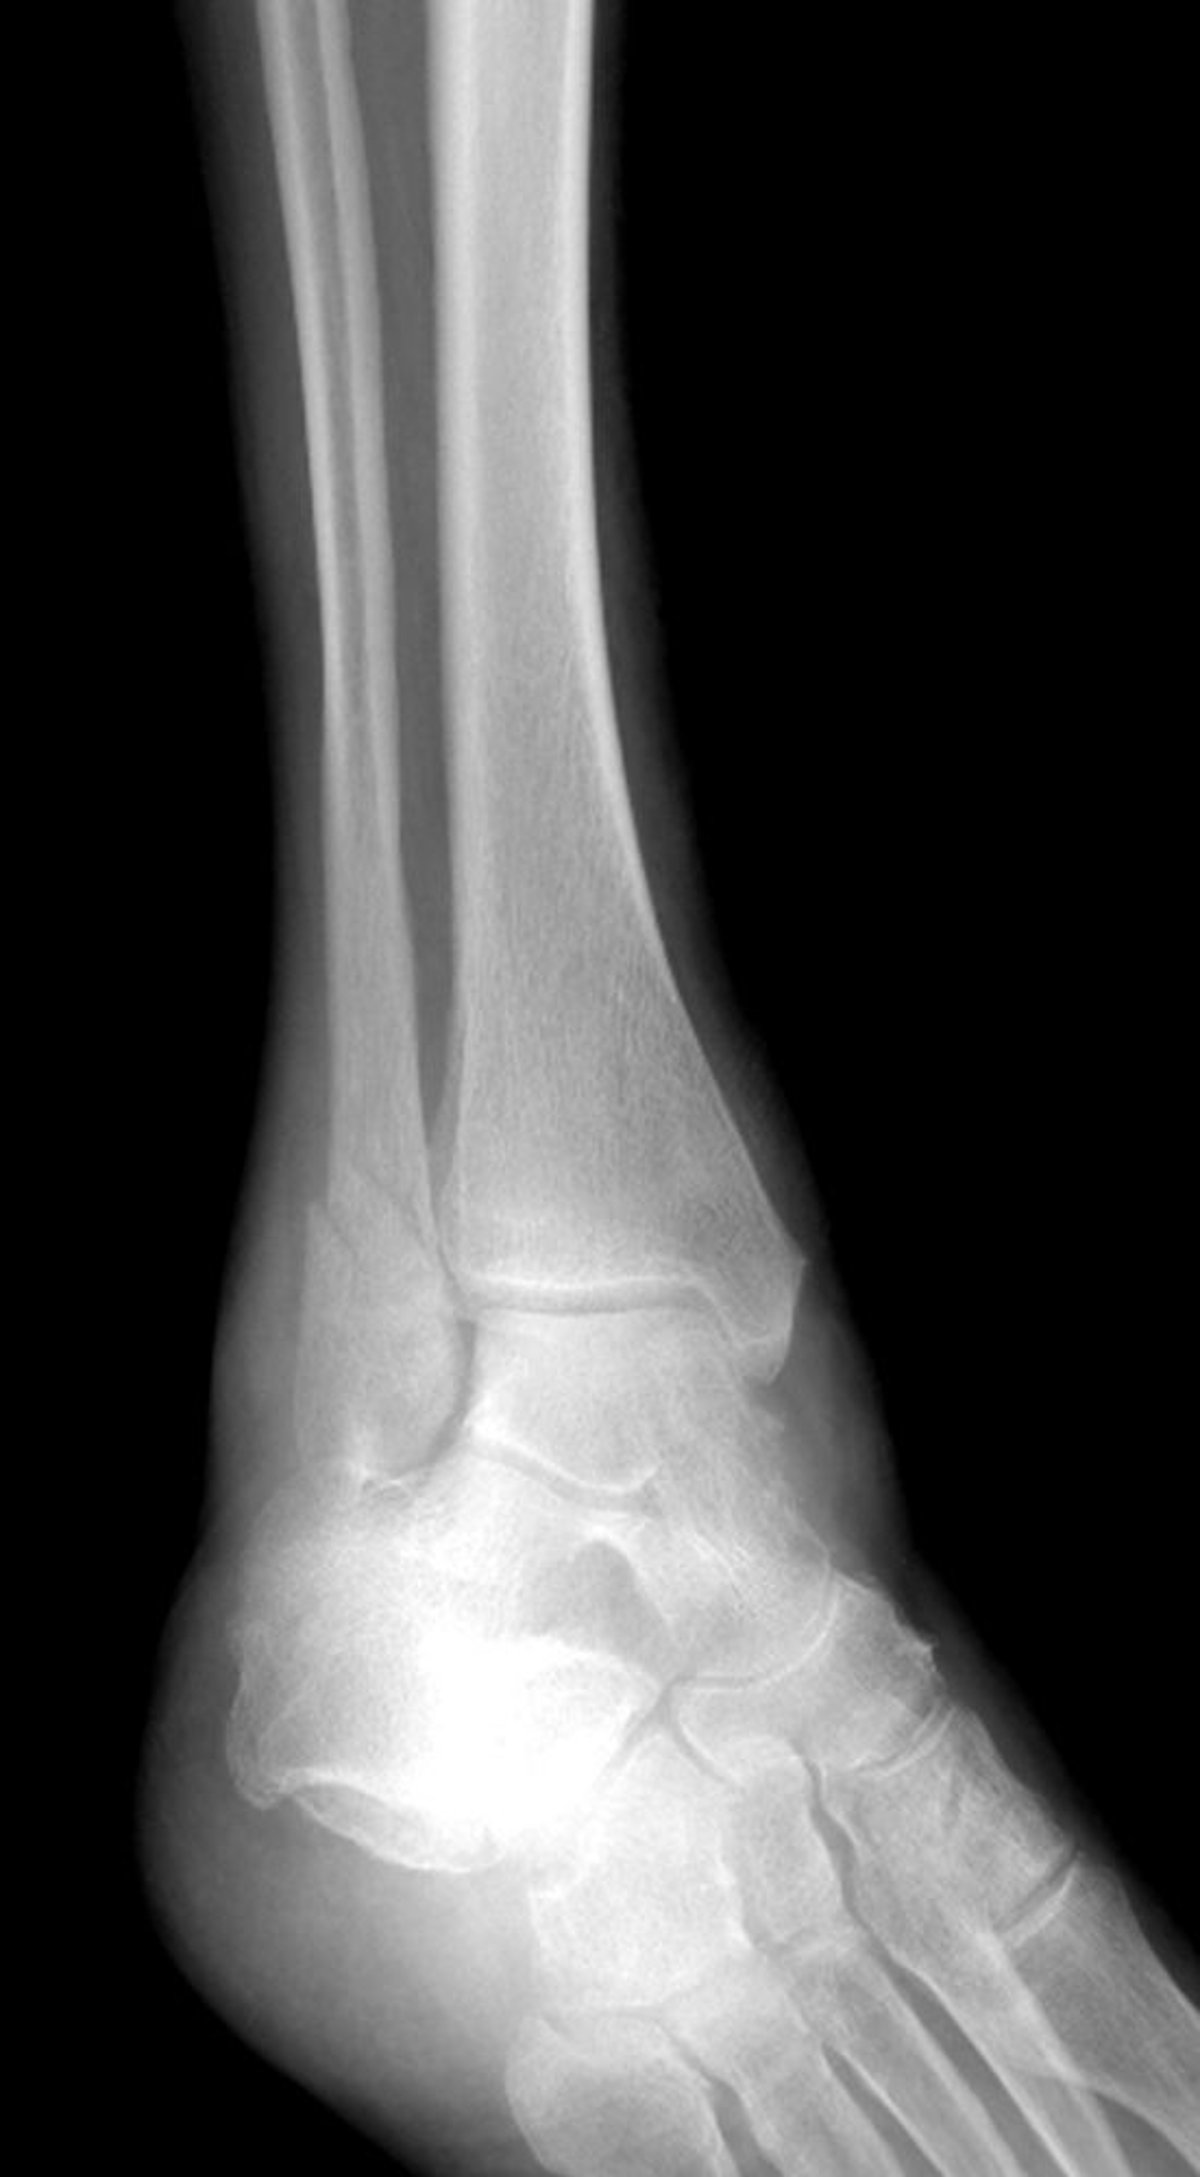

Fracture de la malléole latérale

Cette fracture de la cheville affecte la malléole latérale mais épargne la malléole interne.